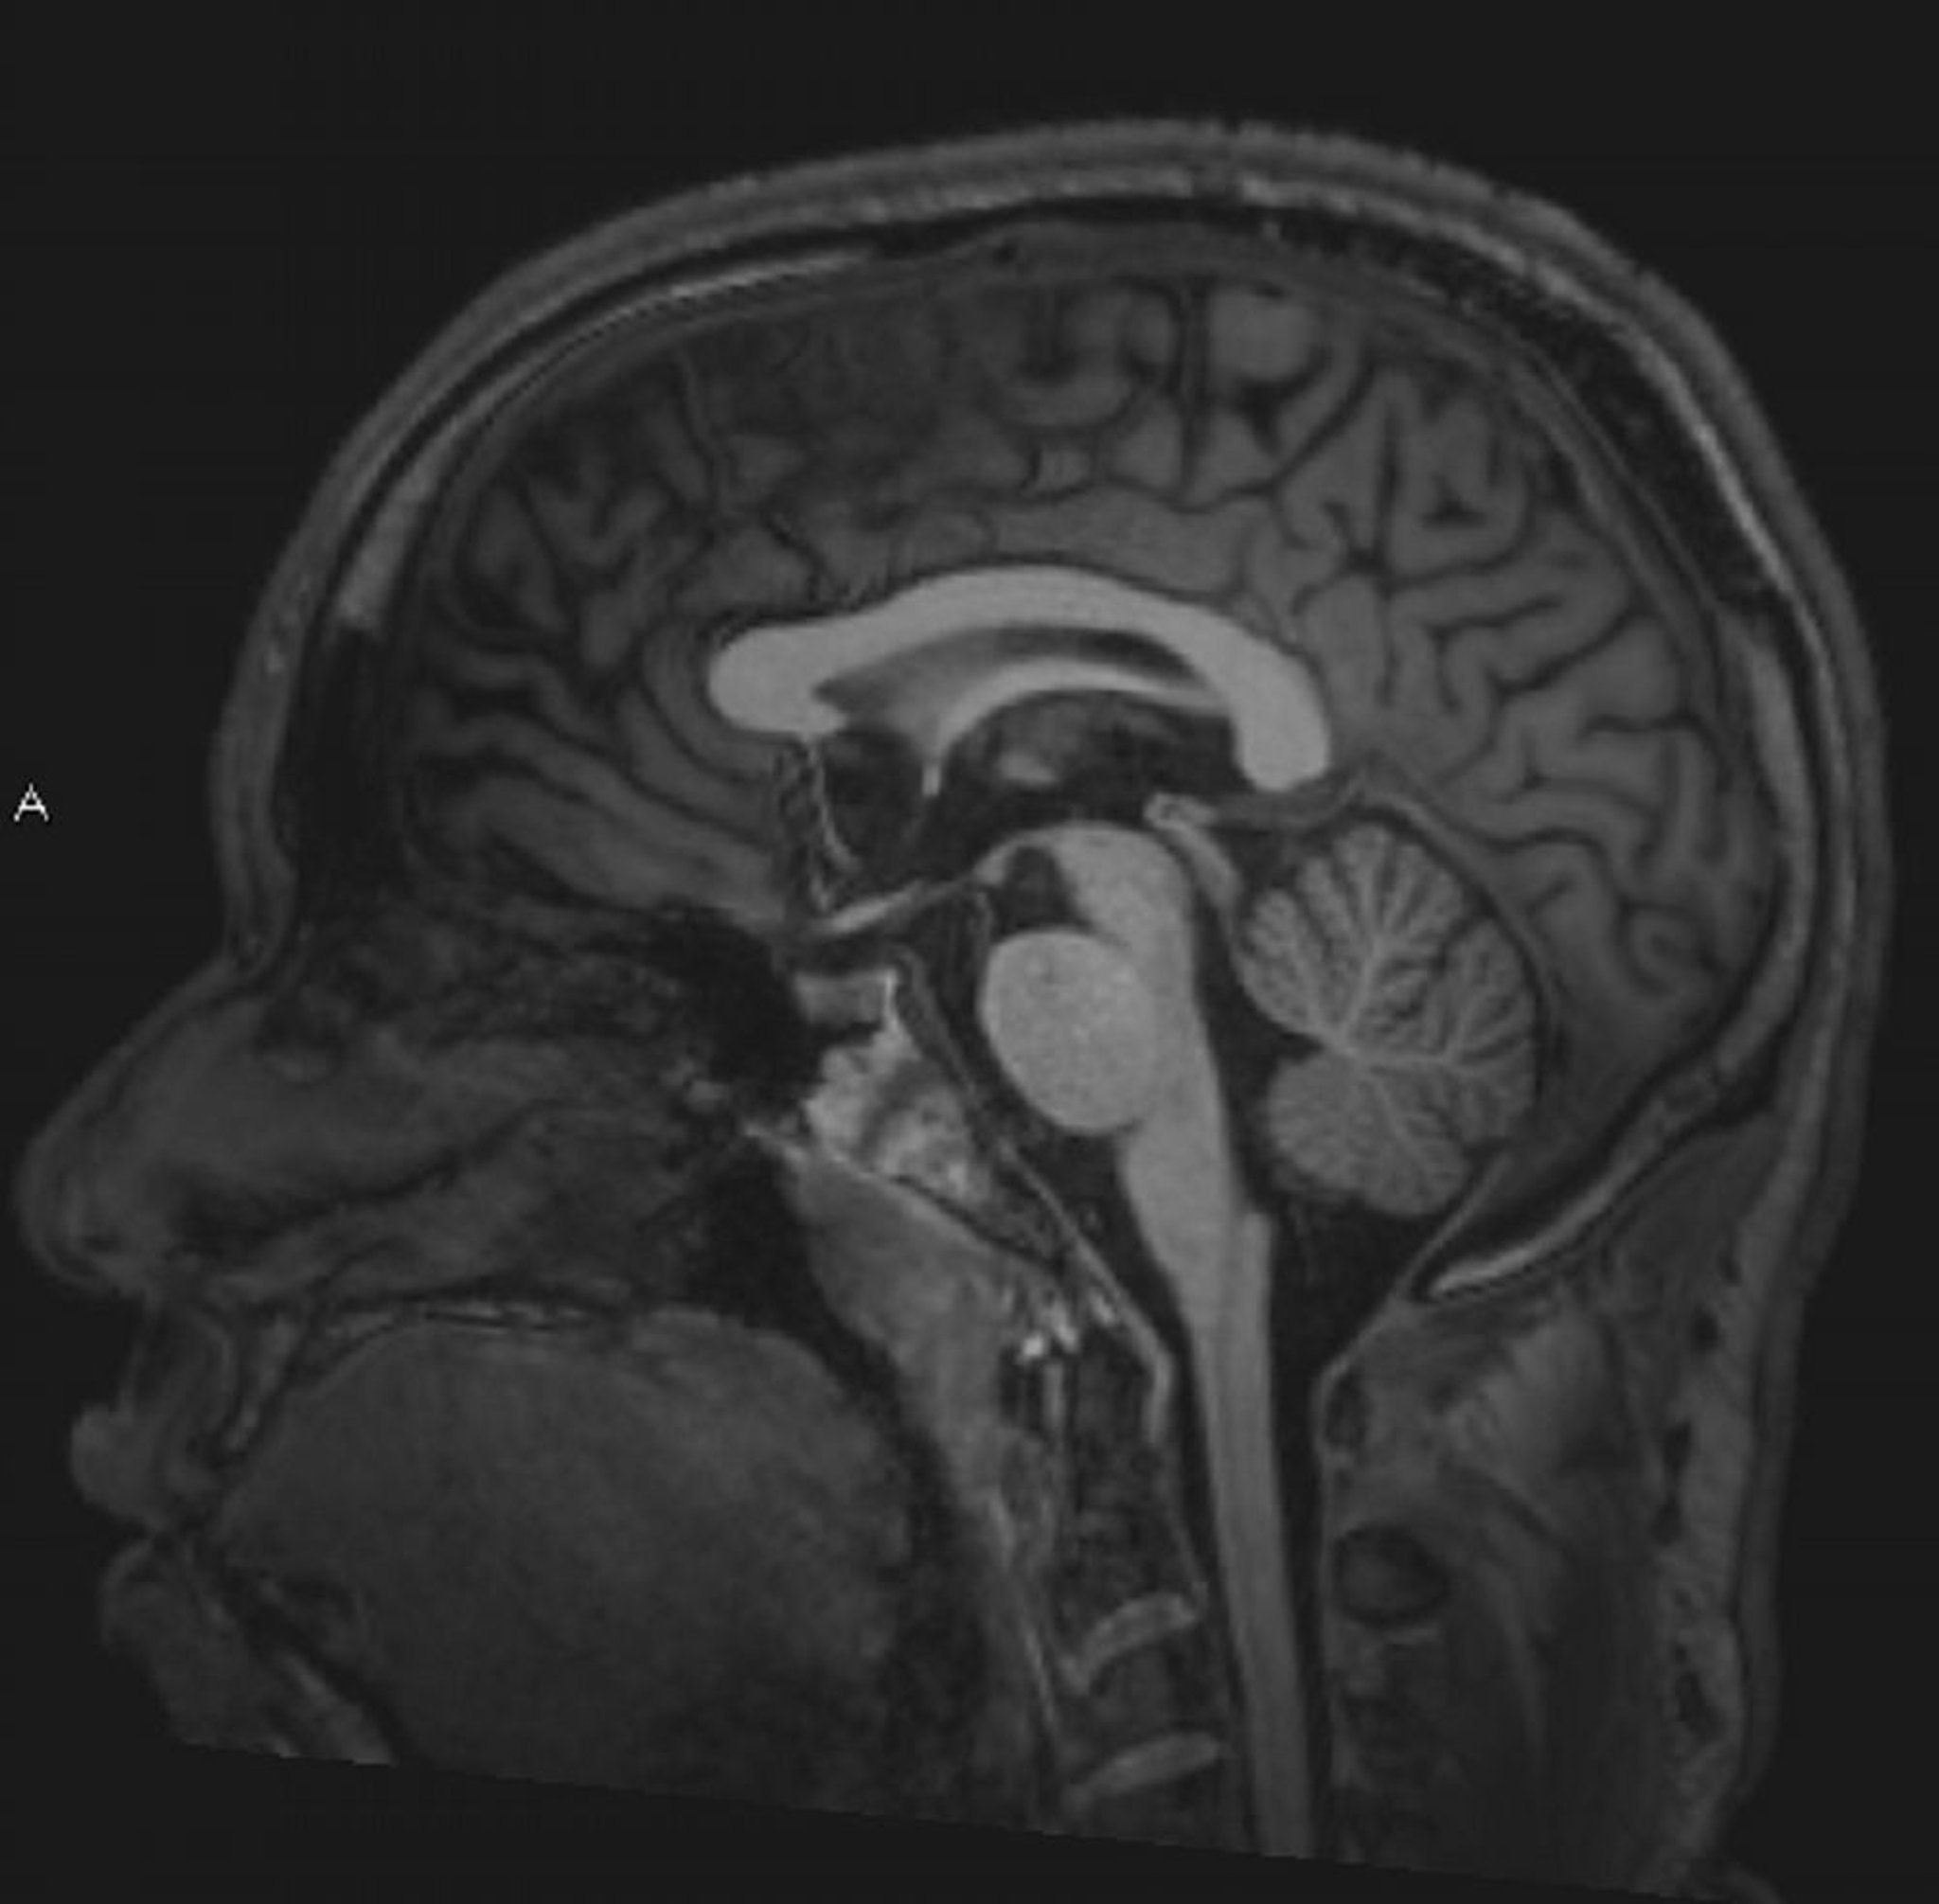

正常な脳MRI画像(矢状断像)―スライド4